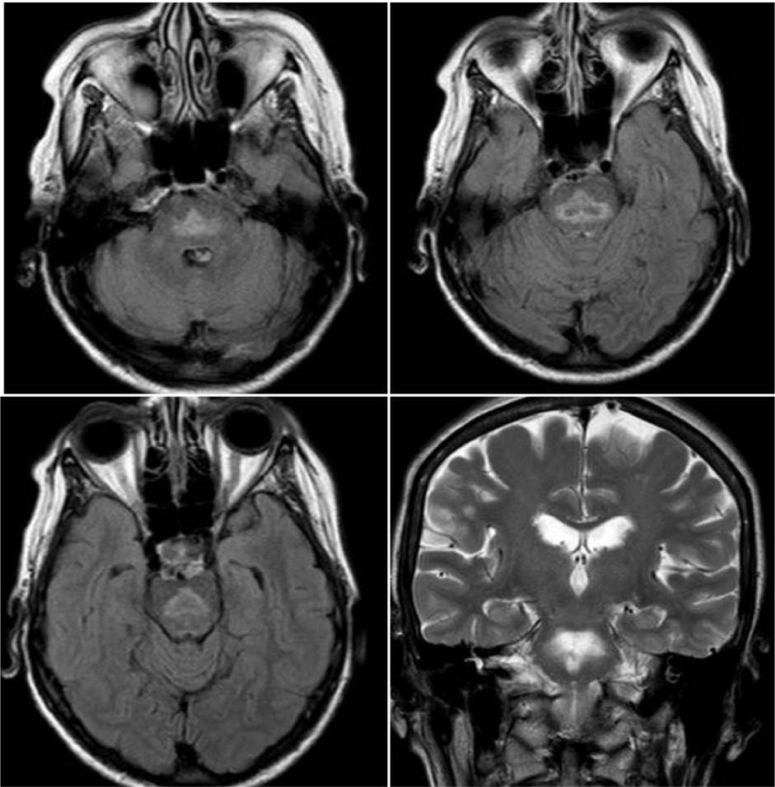

This report aims to present an elderly woman with persistent delirium after hospitalization for lethargy secondary to hyponatremia. The diagnosis of pontine myelinolysis was made and there were no characteristic neurological manifestations such as pupillary changes or spastic tetraparesis. Hallucinations and personality changes were the clues to the diagnosis and should be considered an atypical manifestation of pontine myelinolysis.